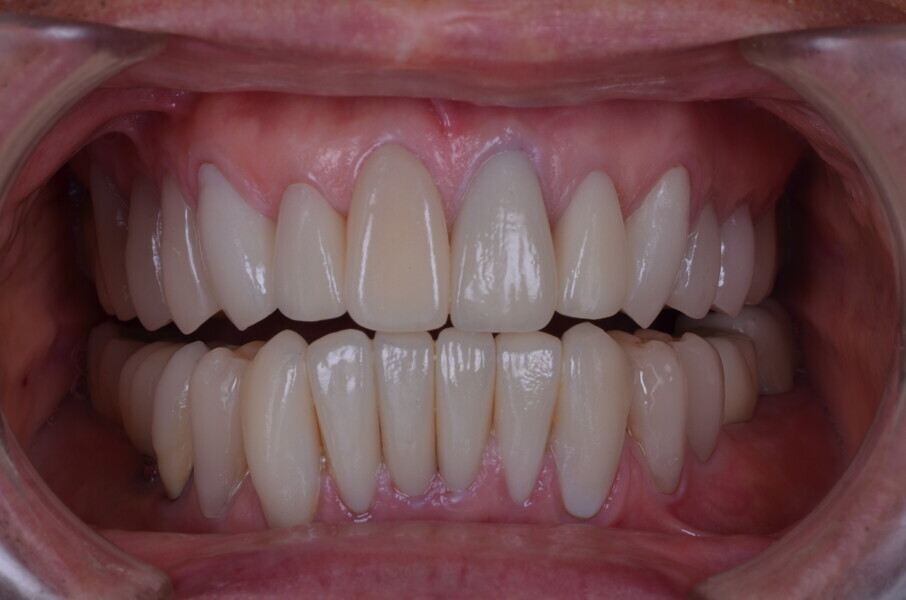

Figure 27 Anterior guidance